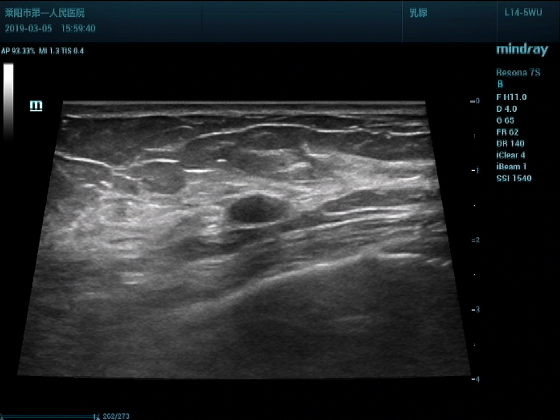

超声入门贴994--乳腺纤维瘤(弹性成像)